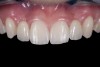

(20.) Facial view of final single-wing, modified zirconia resin-bonded bridges.

Figure 20

(21.) Smile view.

Figure 21